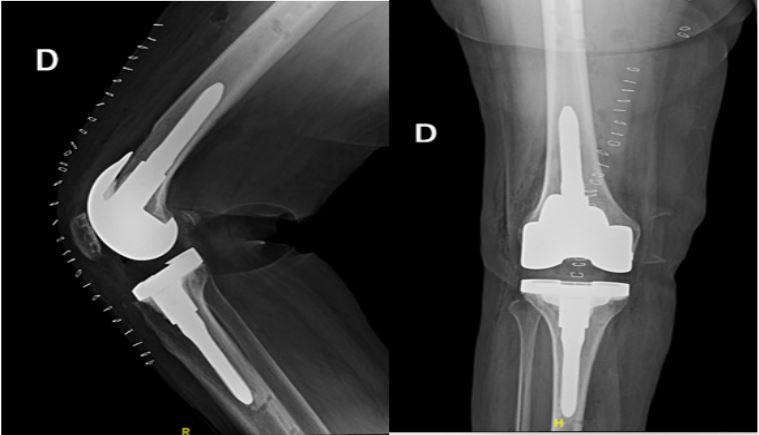

Figure 1 and 2: Pre-operative implants XR and CT scan.

In 2019, a 67-year-old woman underwent Total Knee Arthroplasty (TKA) with kinematic alignment technique at another medical facility due to right knee pain stemming from arthrosis, diagnosed through clinical examination and X-ray imaging (grade 3, Kellgren and Lawrence classification). Post-surgery, she faced challenges with intensive rehabilitation due to persistent anterior knee pain during both active and passive mobilization, resulting in a loss of 35 degrees of extension, swelling, and difficulty in walking. A Knee Society Score (KSS) was administered to her resulting in 20/100.

In 2021, she was diagnosed with patellofemoral malalignment and subsequently underwent patellofemoral arthroplasty to address patellar tracking issues. Unfortunately, she continued to experience discomfort postoperatively, impeding her physiotherapy efforts.

In September 2023, the patient presented to our institution with stiffness and severe knee pain, significantly limiting her daily activities. She reported a Visual Analogue Score (VAS) pain rating of 8/10 and was taking anti-inflammatory medication. Her knee Range of Motion (ROM) was restricted to 35°-85° due to mechanical blockage, indicating potential issues with the implant. To rule out a prosthetic joint infection, we conducted laboratory tests based on the 2018 MSIS criteria, including erythrocyte sedimentation rate, C-reactive protein, procalcitonin, blood count with formula and joint aspiration, all of which yielded negative results [4].

The CT scan showed no signs of loosening but there was evidence of an oversized femoral component in both mediolateral and anteroposterior planes leading to a patellofemoral overstuffing, according to methods of quantifying Patello-Femoral Joint (PFJ) overstuffing produced by Kemp et al. [5]. PFJ overstuffing has been shown to potentially affect the lever arm provided by the quadriceps mechanism in the knee stretching the patellar tendon, altering the contact forces between the implants, and thus leading to a decreased strength, limitated range of motion and giving pain. The anteroposterior PFJ size is given by a combination of parameters such as Anterior Patellar Displacement (APD), Anterior-Posterior Femur Diameter (APFD), Anterior Femoral Offset (AFO), and Posterior Femoral Offset (PFO) and consequently a modification of these parameters alters the patello-femoral tracking. In facts, restoring the anatomic dimensions of the PFJ is recommended, keeping the surgeon within a safe margin of error [6]. Furthermore, mediolateral oversizing is a factor considered to be predictable of poor results in TKA despite it is difficult to obtain optimal fit between the implant and bone [7].